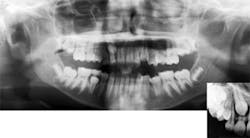

Other findings also often require orthodontic intervention. Posterior crossbites, whether unilateral or bilateral, require orthodontic treatment to correct. Early exfoliation of deciduous teeth (such as lower primary canine exfoliation upon eruption of permanent lateral incisor), or delayed eruption of permanent teeth may also warrant orthodontic involvement to allow for a proper and stable eruption of permanent teeth. Mobility of the permanent dentition, which may present itself in incisors as ectopic canines resorb their roots (see Figure 2), can also be a cause for concern and requires additional evaluation.